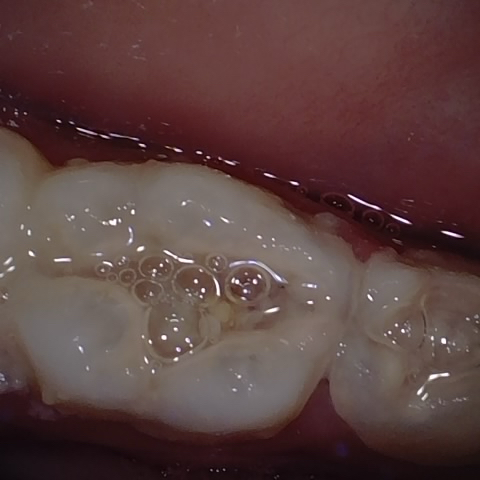

NHD25463

Annotated as "Good"

Original Image Rendering Image